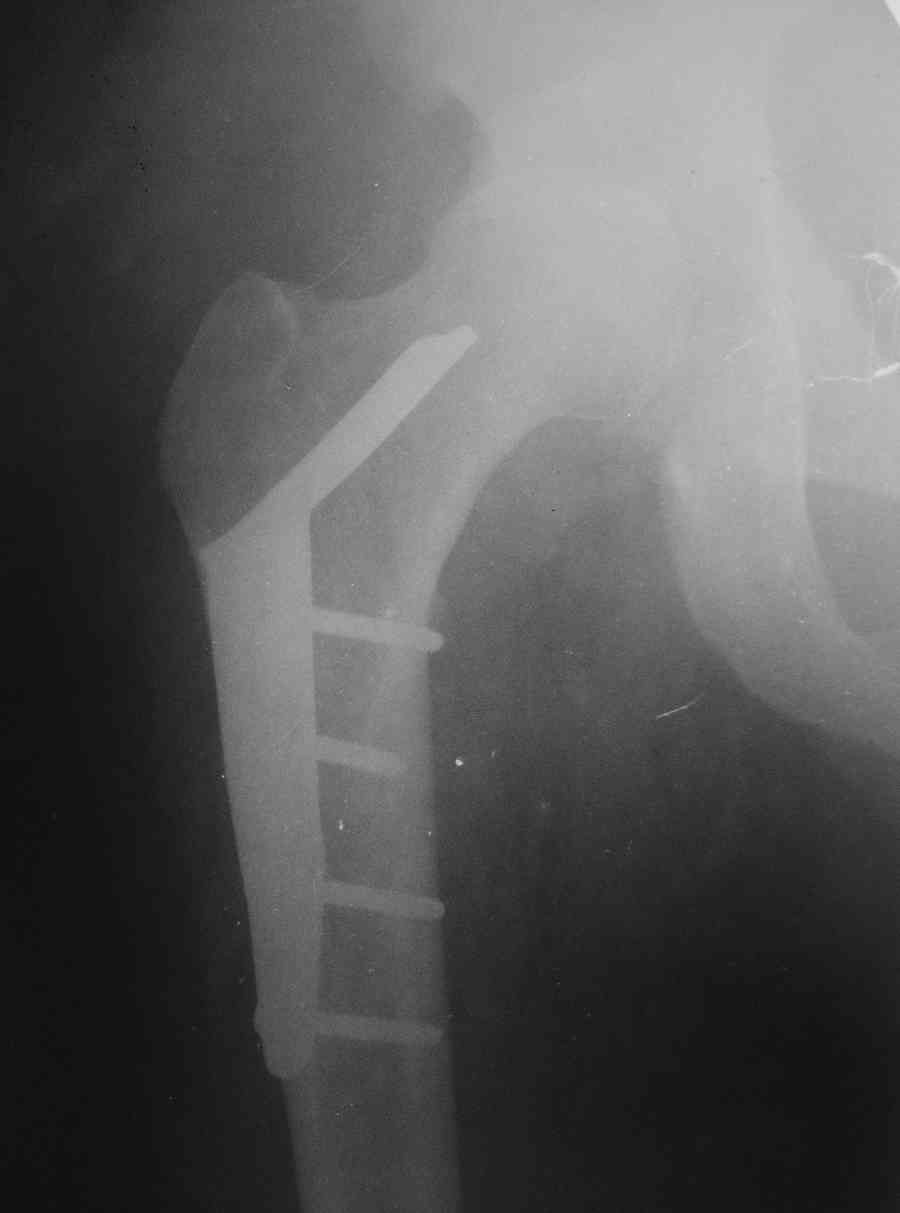

Застарелый вывих бедра

К нам обратился житель Казахстана с застарелым вывихом бедра.

Травма год назад, вместо синтеза заднего края казахскими умельцами установлена клинковая пластина, через 6 мес удалена. Больной ходит с тростью,сгибание в т-б 90, разгибание 170, укорочение 5 см, боли не выражены, анальгетиками не пользуется. Настроен на эндопротезирование в клинике, где есть опыт подобных операций (возможно за рубежом). Наш план: аппарат таз-бедро, постепенное низведение бедра, "октопус" с пластикой. Но с такими большими дефектами мы не сталкивались. Есть вариант сначала аппарат, затем реконструкция впадины, протез обычный через 4-6 мес. Есть мнение не восстанавливать длину. Будем признательны за полезные советы. Было бы интересно посмотреть пример.